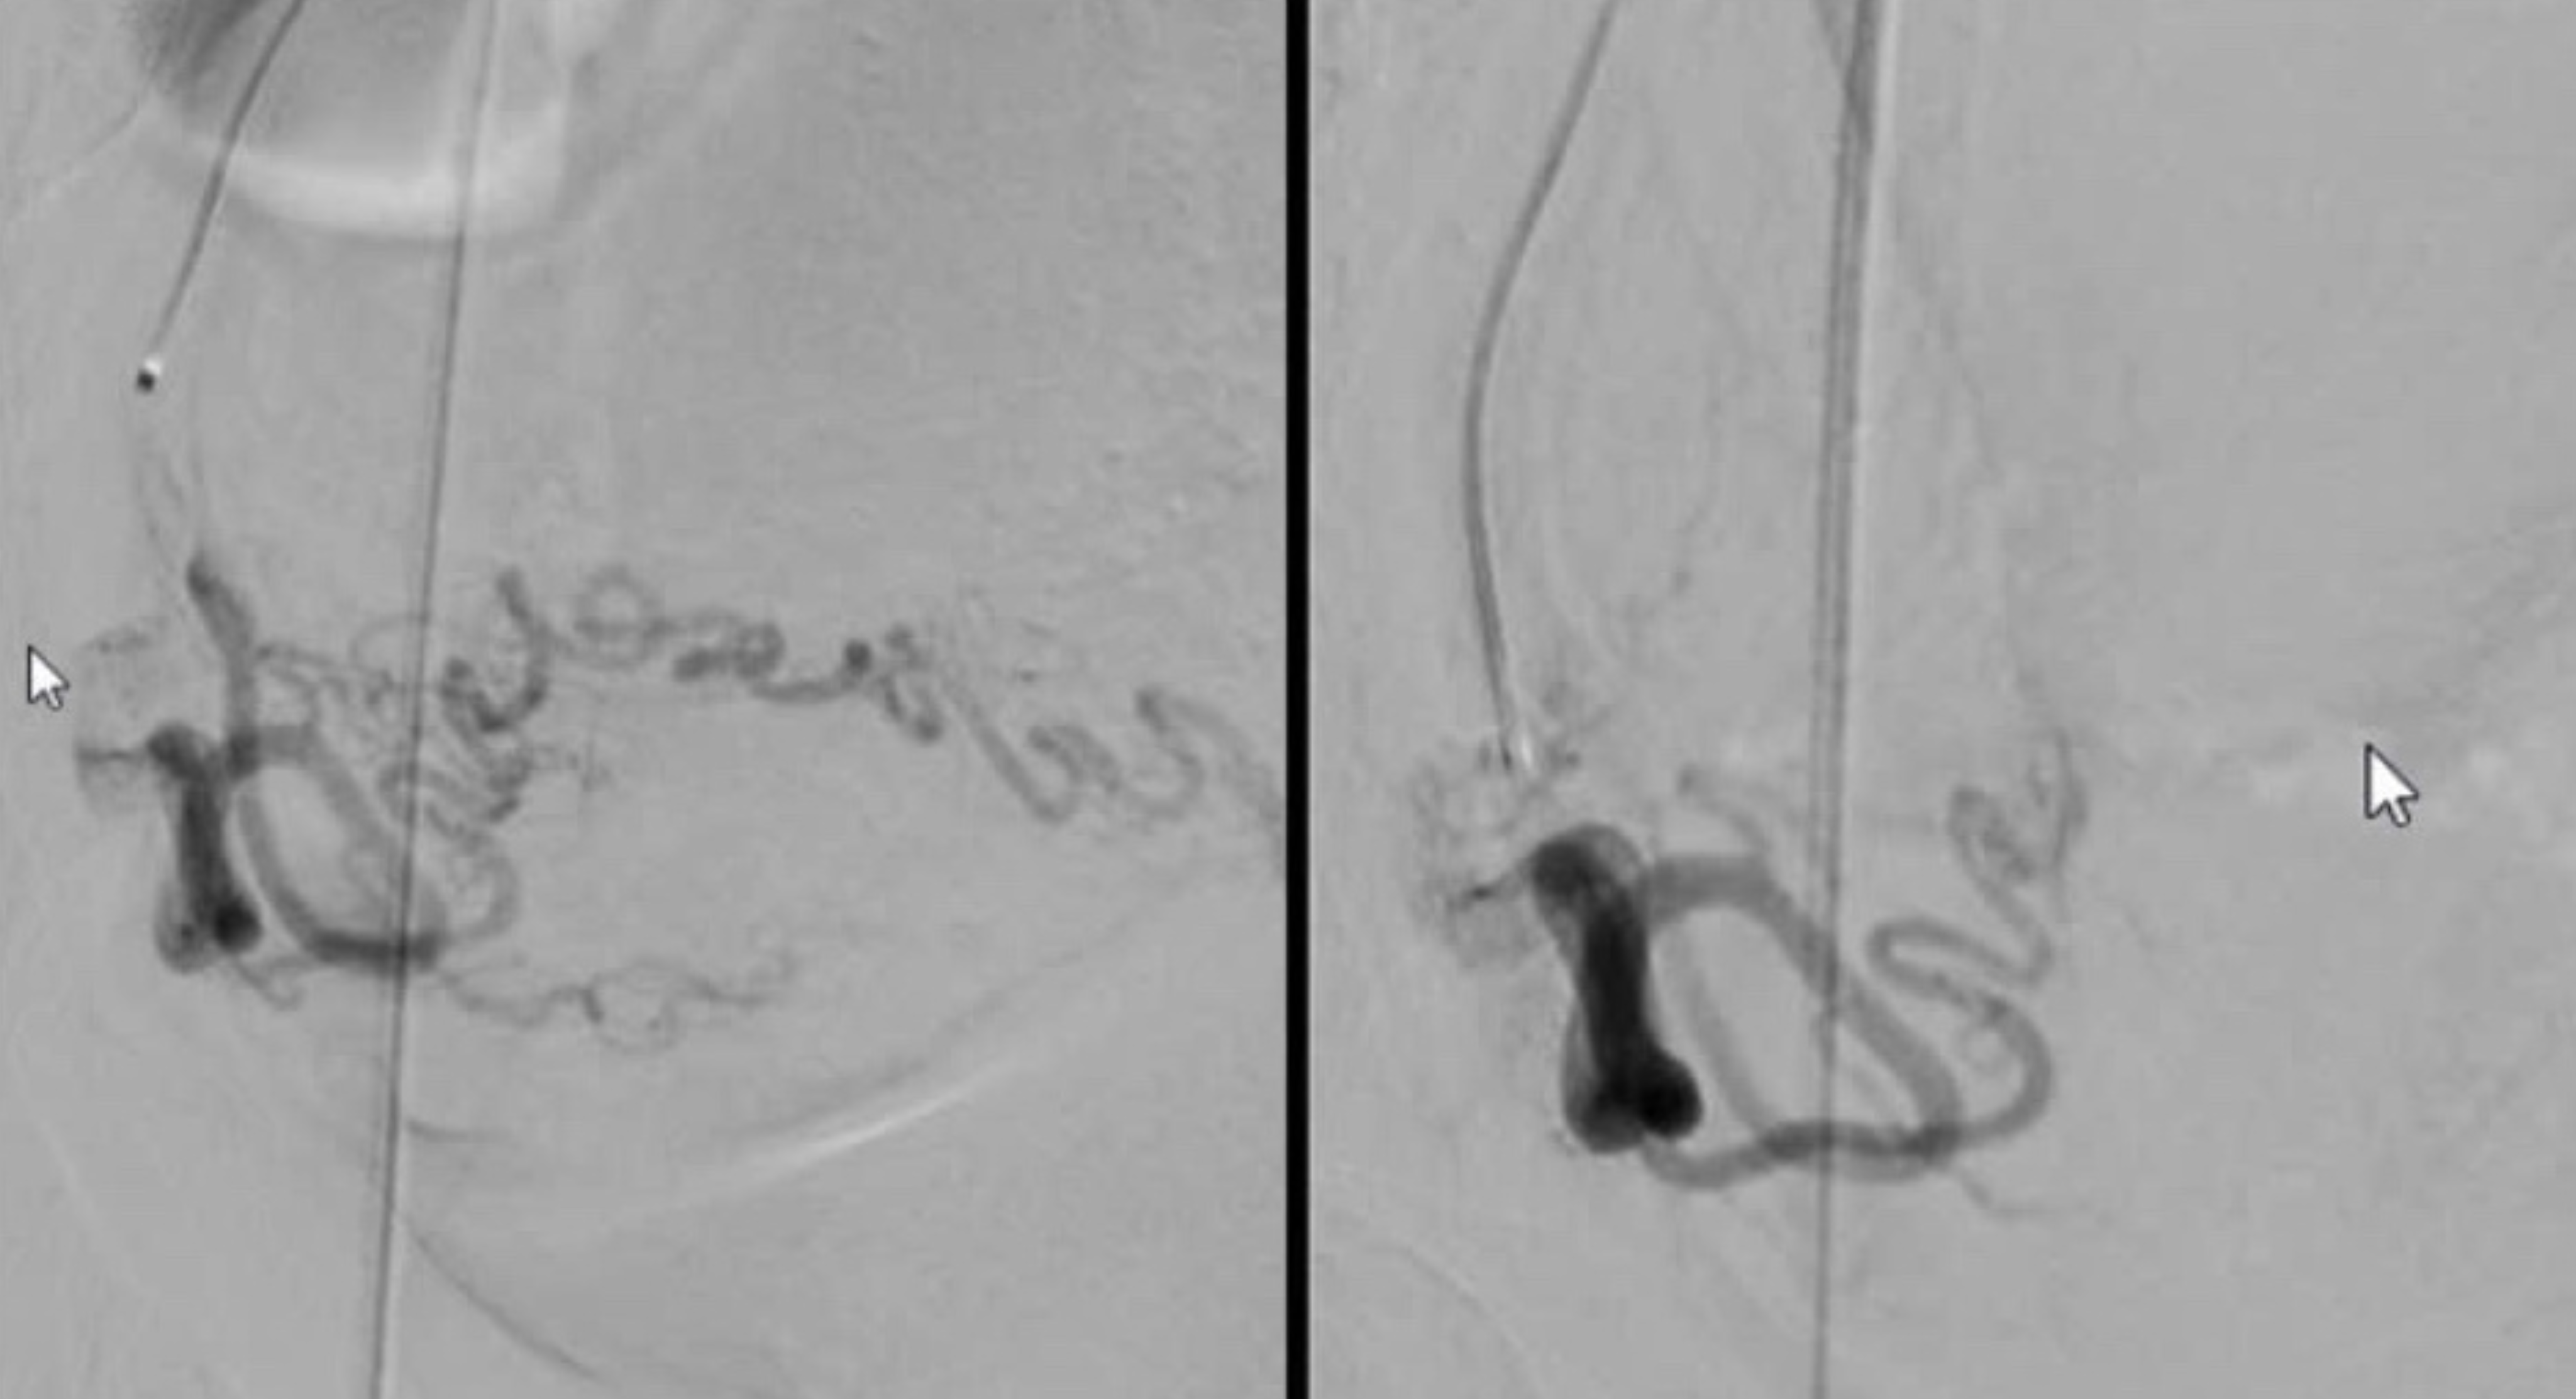

![]() ![]() |

Hình trước và sau khi thực hiện thủ thuật nút mạch tử cung bên phải - trái. |

“Khối u to chèn ép đường đại tiện gây táo bón, ngoài ra khiến bệnh nhân dễ bị xuất huyết nên có hiện tượng rong kinh. Do vậy, sau khi thực hiện thủ thuật tắc mạch, khối u teo nhỏ và không còn chèn ép, theo đó các triệu chứng cũng được cải thiện”, bác sĩ Danh giải thích.